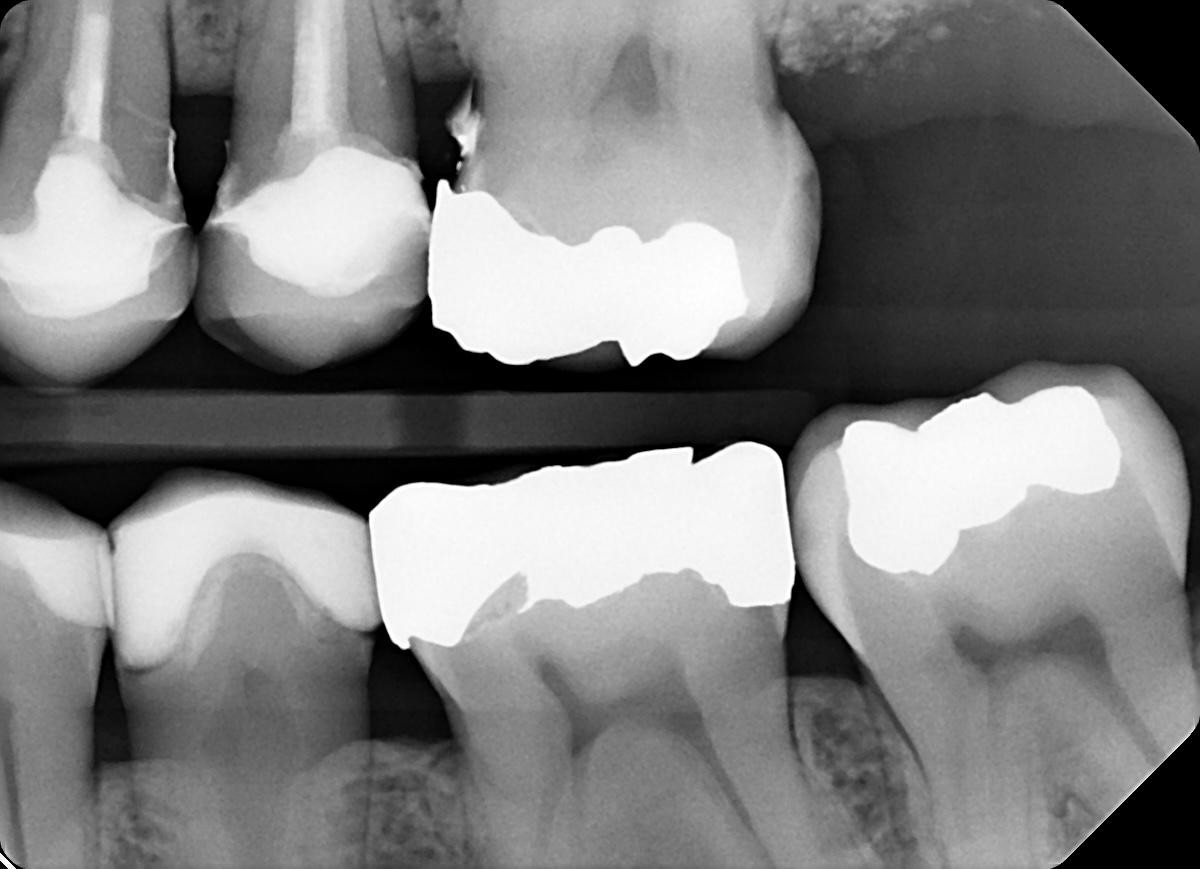

6. What option can explain the crowns in the X ray bellow?